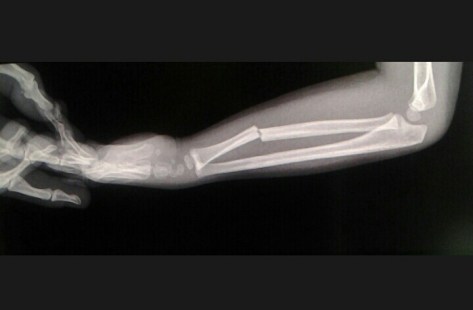

Keadaan saat awal operasi (durante op) bagian ujung kaki (distal) tampak berwarna pucat kebiruan. Tidak dijumpai perdarahan aktif. Hematom ada diantara jaringan bawah kulit (subkutis), diantara otot yang tercabik-cabik. Dilakukan tindakan meluruskan kembali tulang, re-aligment sekaligus dilakukan debridemen. Posisi tulang yang pecah fragmented dilakukan re-aligment. Selanjutnya dilakukan fiksasi tulang (external fixation). Penutupan jaringan lunak (soft tissue) dilakukan sedapatnya dengan tarikan regang yang sedikit (minimal tension). Diakhir operasi ujung kaki mulai tampak kemerahan kembali.

Patah tulang tibia (tibial fracture) adalah patah tulang panjang yang paling sering dijumpai khususnya pada bagian batang tulang shaft (plateau, shaft dan plafon). Dari mekanismenya dibedakan menjadi 2 jenis yaitu low energy fracture pattern dan high energy fracture pattern.

Dari mekanisme low energy umumnya didapatkan alibat cidera tidak langsung (torsional injury) dengan ciri khas didapatkan patah tulang fibula pada level yang berbeda, sedangkan untuk mekanisme high energy injury umumnya dari benturan langsung yang seringkali berupa patahan dengan bentuk baji (wedge) atau short oblique dengan bagian yang terpecah (kominutif fragment).

Pengobatan patah tulang tibia dapat pula dilakukan melalui operasi dengan beberapa indikasi berupa posisi tulang yg tidak baik selah dilakukan reposisi tertutup (unacceptable alignment with closed reduction and gips), cidera jaringan lunak luas yang menyulitkan perawatan, patah tulang dengan tipe segmental dan kominutif.